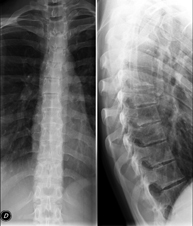

- Thoracic spine X-ray

This technique uses X-ray rendered imaging to examine the thoracic spine. Indicated for: trauma, back pain.

Tècnica que usa els raigs X a través de la qual s'obtenen imatges de la columna dorsal per al seu estudi. Indicacions: traumatisme, dolor, escoliosi. - Esofagograma